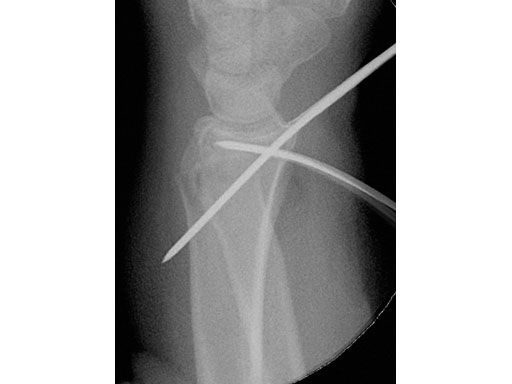

22-year-old male fell off a horse while playing polo.

Fig 1a-b Preoperative x-rays.